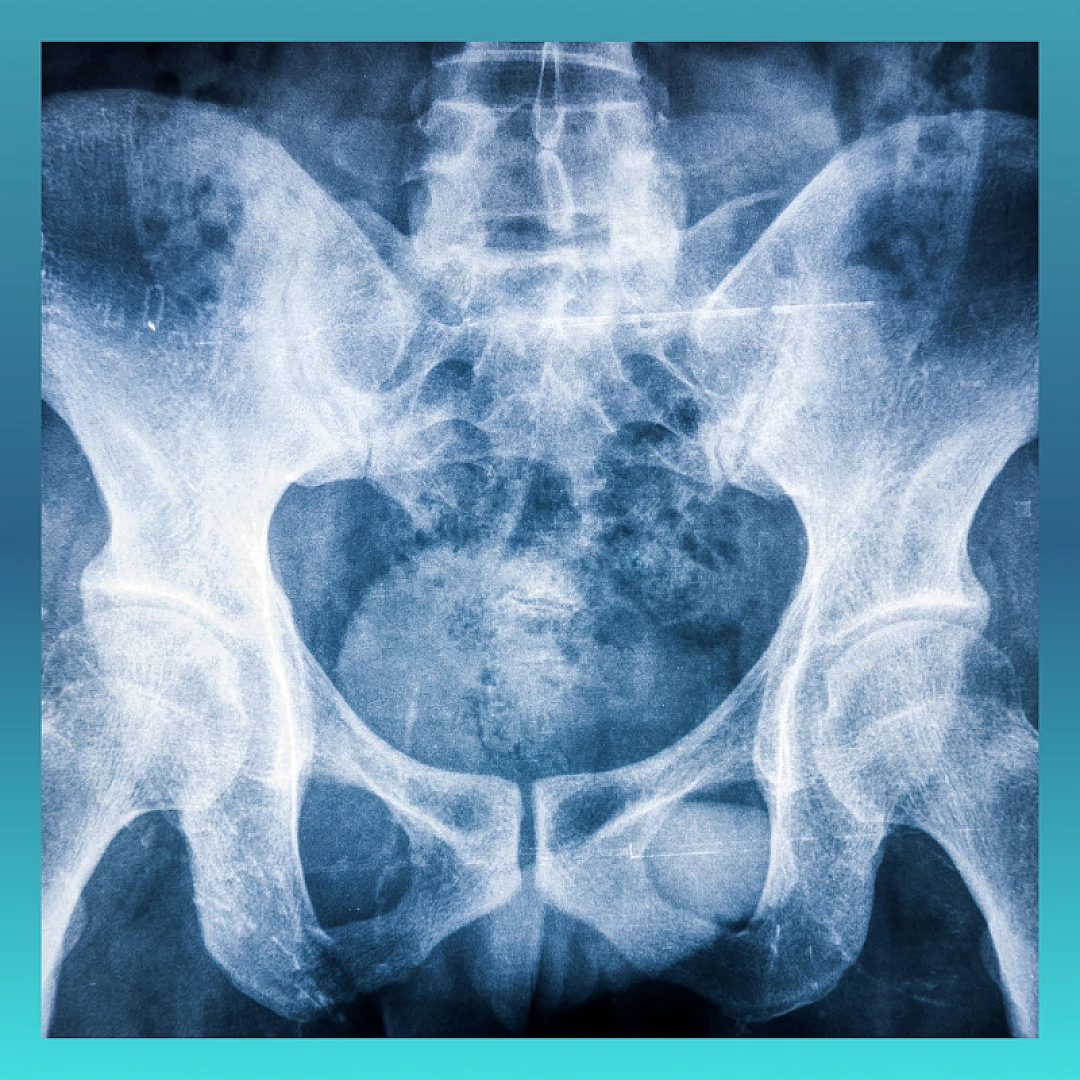

علاج المفصل العجزي الحرقفي

تشخيص اضطراب المفصل العجزي الحرقفي يتطلب تاريخًا شاملاً للمريض وفحصًا جسديًا دقيقًا.

المفصل العجزي الحرقفي يؤدي دورًا حيويًا في امتصاص الصدمات ومنع وصول قوى الصدمة إلى العمود الفقري. أسباب ألم مفصل الحوض الصلب غير معروفة، ولكن هناك عوامل متعددة تؤدي إلى هذا الألم في المفصل، بما في ذلك الصدمات والإصابات.

يمكن أن تشمل أسباب ألم مفصل الحوض الصلب الأخرى ما يلي:

• التهاب المفصل

• ترخي الأنسجة بسبب الحمل

• عملية جراحية في أسفل الظهر

• مرحلة ما بعد الولادة

• الحالات الالتهابية النظامية

• العدوى في المفصل